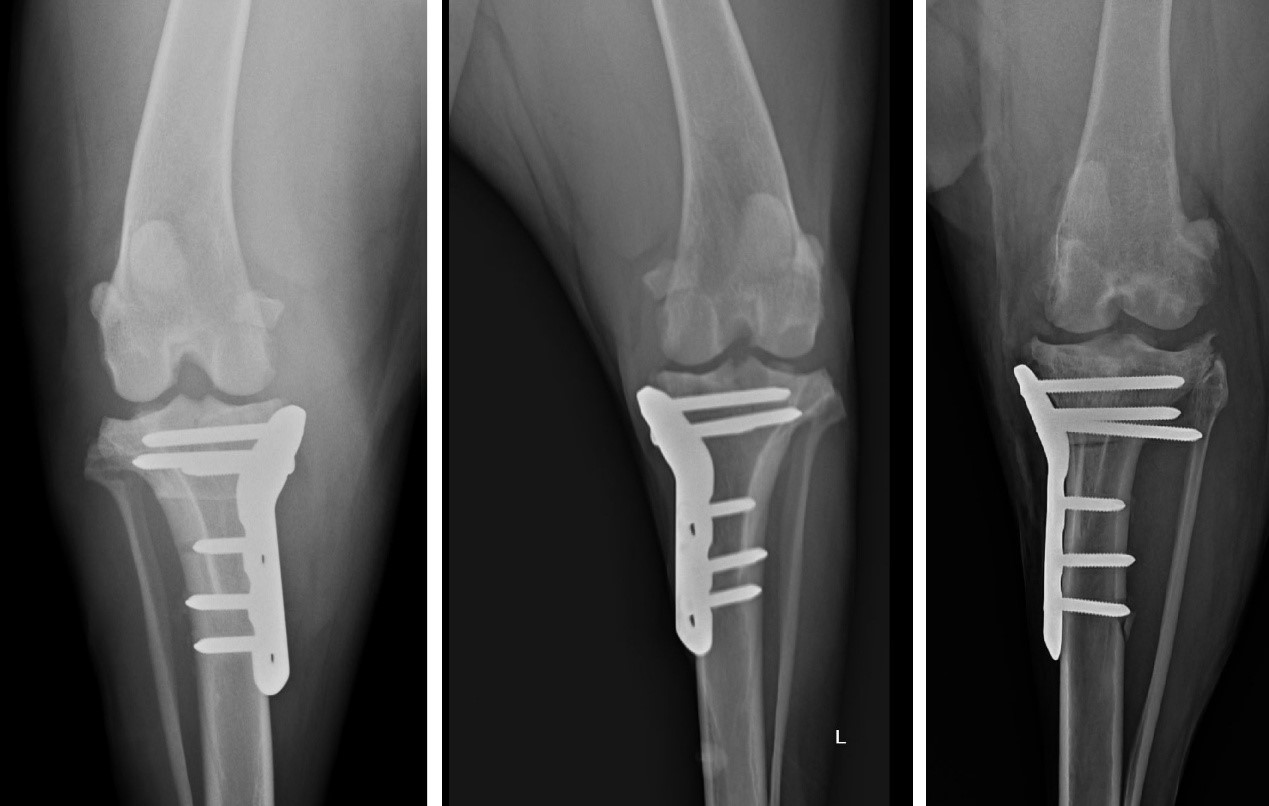

TPLO (Tibial Plateau Leveling Osteotomy) 是目前國際公認治療前十字韌帶斷裂的黃金標準手術。

它的原理非常巧妙: 既然韌帶斷了,我們不再執著於修補那條脆弱的韌帶,而是透過幾何力學的改變,將脛骨切開並旋轉角度,改變膝關節受力的平臺。術後,狗狗的膝蓋不再需要依靠前十字韌帶就能在行走時保持穩定。

一張含有 X 光影像, 醫學影像, X 光照相術, X 光 的圖片AI 產生的內容可能不正確。